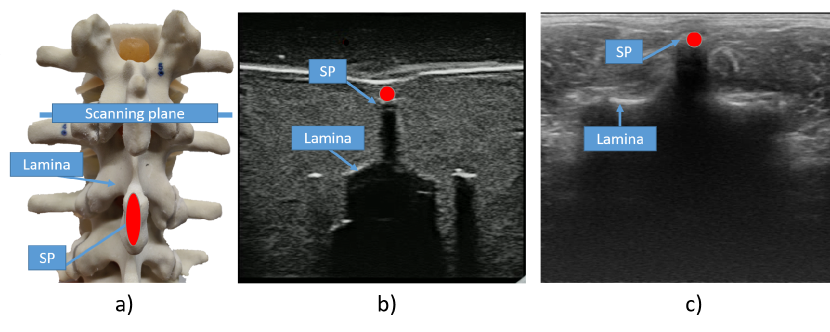

This limitation can be overcome by using computer control to locate these features and guide a robotic arm that manipulates an ultrasound probe. To ensure that the spine is always in the probe’s field of view, the robot needs to follow the spine’s profile during scanning so that the vertebrae are located in the center of the ultrasound image. A spinous process is located in the middle of the vertebrae and indicates the vertebra’s presence in the image, whereas its absence indicates an intervertebral gap (see Fig. 1). These features are utilized for 3D spine reconstruction and scoliosis assessment by measuring the angle of the spinal curvature.

Figure 1: Spinal anatomical features on phantom and US images of phantom and human. Lamina and spinous process (SP). a) Spinal features presented at the spinal column phantom, b) Spinal features visible on US images of a phantom, c) Spinal features visible on US images of a human.